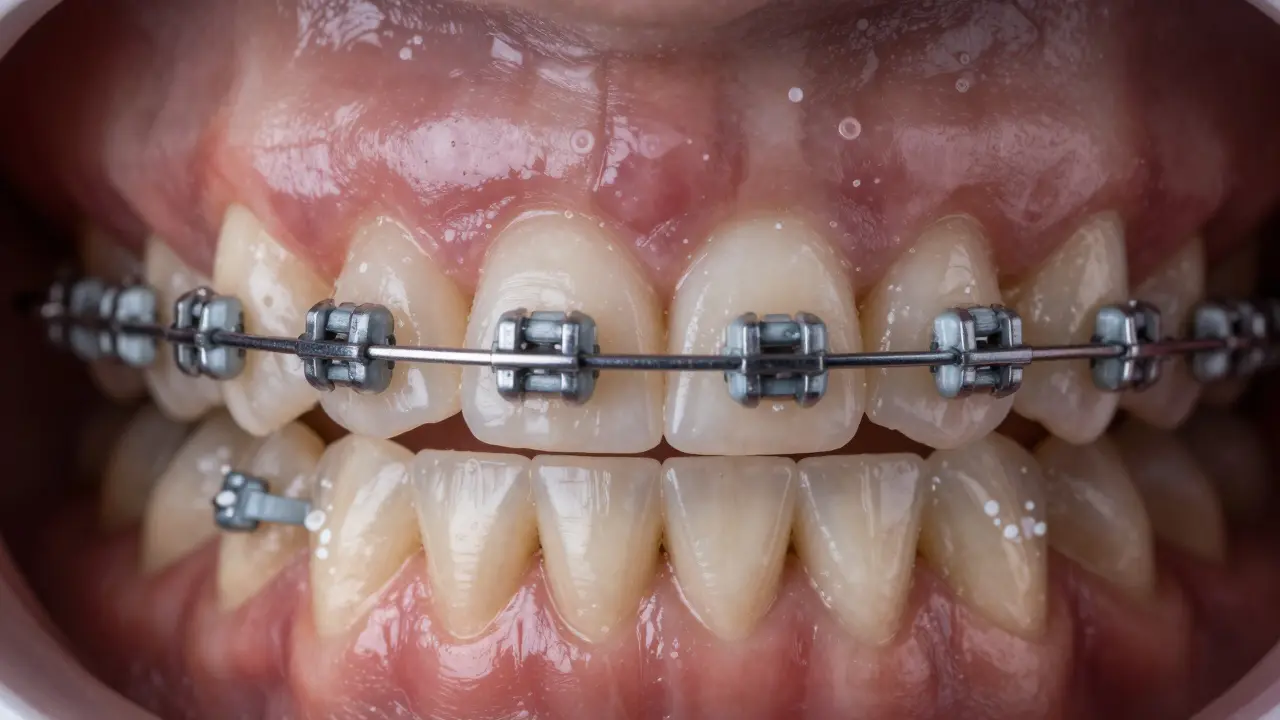

Po rovnátkách mohou zuby trpět poškozením skloviny nebo kariés. V článku najdete kroky k obnově, profesionální léčebné možnosti a domácí péči. Ujistěte se, že pravidelně navštěvujete zubaře a dodržujte doporučenou hygienu.